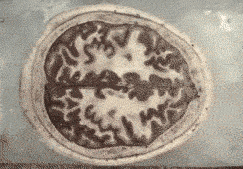

10.大脑切片

这张动图是根据真实切片标本制成的,展示了人类脑部组织的横截面,原标本共包含了700个切片,每个切片的厚度为174um。纤薄的组织切片可帮助人们更好的了解精细的解剖结构。